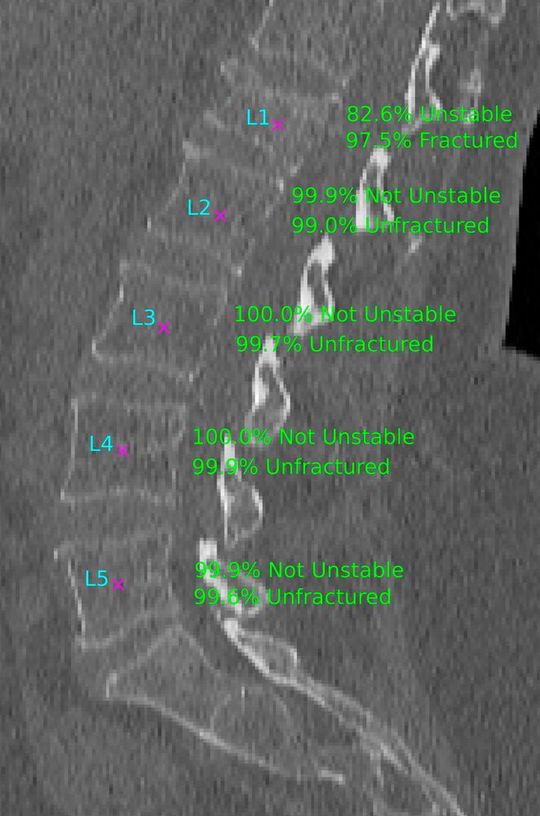

Abb. 2: Laterales Schichtbild der Lendenwirbelsäule zeigt korrekt vom KI-Assistenten automatisch gefundene Mittelpunkte der Wirbelkörper (lila), die genutzt werden, um eine korrekte Bezeichnung der Wirbelkörper (cyan) zu erreichen. Im nachfolgenden Schritt erfolgt die Einstufung der Wahrscheinlichkeit, dass der jeweilige Wirbelkörper frakturiert bzw. instabil ist(© Sektion Biomedizinische Bildgebung, UKSH/CAU)

Abb. 2: Laterales Schichtbild der Lendenwirbelsäule zeigt korrekt vom KI-Assistenten automatisch gefundene Mittelpunkte der Wirbelkörper (lila), die genutzt werden, um eine korrekte Bezeichnung der Wirbelkörper (cyan) zu erreichen. Im nachfolgenden Schritt erfolgt die Einstufung der Wahrscheinlichkeit, dass der jeweilige Wirbelkörper frakturiert bzw. instabil ist